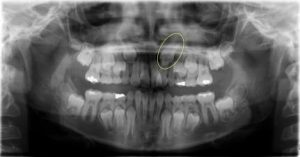

شکل- وضعیت طبیعی دندان نیش در شکل بالا نشان داده شده است.

در حالت نرمال دندانهای نیش فک بالا (ماگزیلاری) آخرین دندانهای ناحیه جلوی دهان هستند که از لثه بیرون میزند (شکل بالا). این دندانها معمولاً در سن سیزده سالگی کاملا بیرون زده و فضای باقی مانده بین دندانهای جلویی فک بالا را میبندند.

تکنیکهای مورد استفاده برای کمک به بیرون زدن دندان نهفته در مورد هر دندان نهفته دیگری در قوس دندانی بالا یا پایین قابل انجام هستند اما در بیشتر موارد برای دندان نیش فک بالا استفاده میشوند. ۶۰% از دندانهای نیش نهفته در سمت کام قوس دندان (به سمت سقف دهان) قرار دارند. بقیه دندانهای نیش نهفته در میانه استخوان پشتیبانی کننده قرار دارد و در بالای ریشه دندانهای مجاور یا در سمت فیشیال (چهره ای) قوس دندانی گیر کرده اند (شکل بالا).